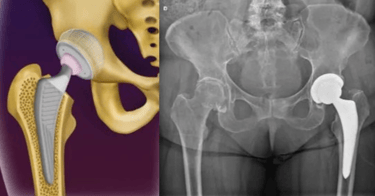

A artrose do quadril é uma condição degenerativa da articulação, que cursa com o desgaste da cartilagem, fazendo com que o paciente apresente dor ao andar e movimentar o quadril.

Faz-se o diagnóstico com RX e Ressonância Magnética.

O tratamento se inicia com medicações analgésicas, perda de peso e Fisioterapia. No entanto, pode-se realizar infiltração com ácido hialurônico na articulação caso o paciente persista com dor na coxa ou dor no quadril.

Com o avanço dos materiais utilizados na cirurgia e nas técnicas cirúrgicas, o paciente volta a ter uma vida normal, praticamente sem limitações após a cirurgia. As próteses mais modernas têm uma durabilidade de aproximadamente 25 anos, permitindo que mesmo pacientes mais jovens possam ser submetidos a essa cirurgia.

Faz-se o tratamento com a prótese de quadril em casos avançados, ou seja, em que houve colapso/retificação da cabeça femoral ou quando já existe artrose instalada.

Já em casos avançados, realiza-se o tratamento com a cirurgia de prótese do quadril, na qual substitui-se a articulação com desgaste por uma articulação metálica, que irá reproduzir os movimentos e funções de um quadril normal.